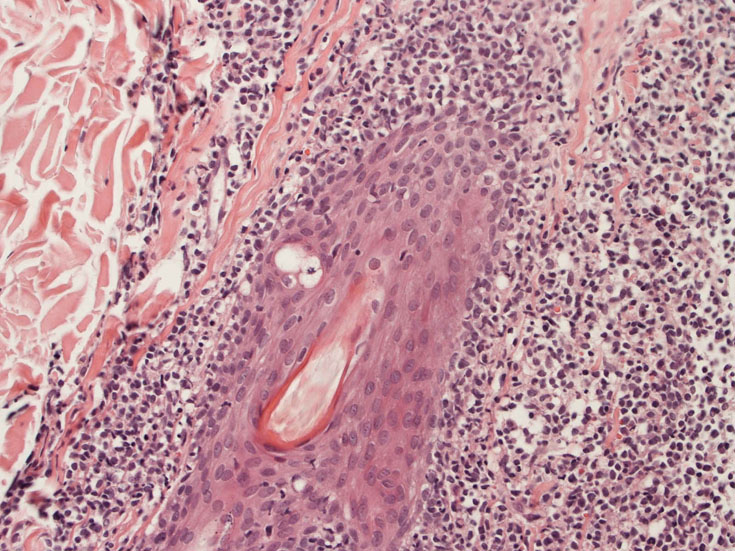

リンパ節病理組織所見

罹患リンパ節の基本構造は消失し腫瘍細胞のびまん性増殖で置換されている。非腫瘍性の小リンパ球(CD3+, CD4/8+)が濾胞様に散在して残る(Fig.01)。不整型または類円形の明るい核をもつmedium-sizeのリンパ球様細胞が密に増殖している。細胞質は乏しい(Fig.02)。CD68陽性macrophageが多く混在する部分が認められた。

Fig03, Fig04は腫瘍細胞の拡大像。大型異型細胞の出現が認められる。腫瘍細胞はCD4+, CD56+, CD123+